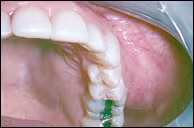

A 33-year old woman presented with dull pain associated with an expansile mass involving the left maxillary vestibule.